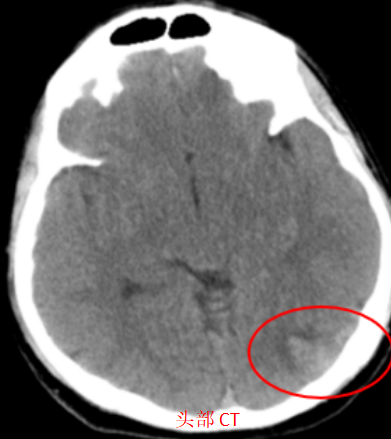

头部 CT 显示:左枕叶有少量出血。这个结果立刻引起了血管组纪祯龙、樊欣鑫两位医生的高度警惕——对于没有高血压和外伤的年轻人来说,这样的自发性出血,往往暗示着更复杂的问题:脑动静脉畸形(AVM)。